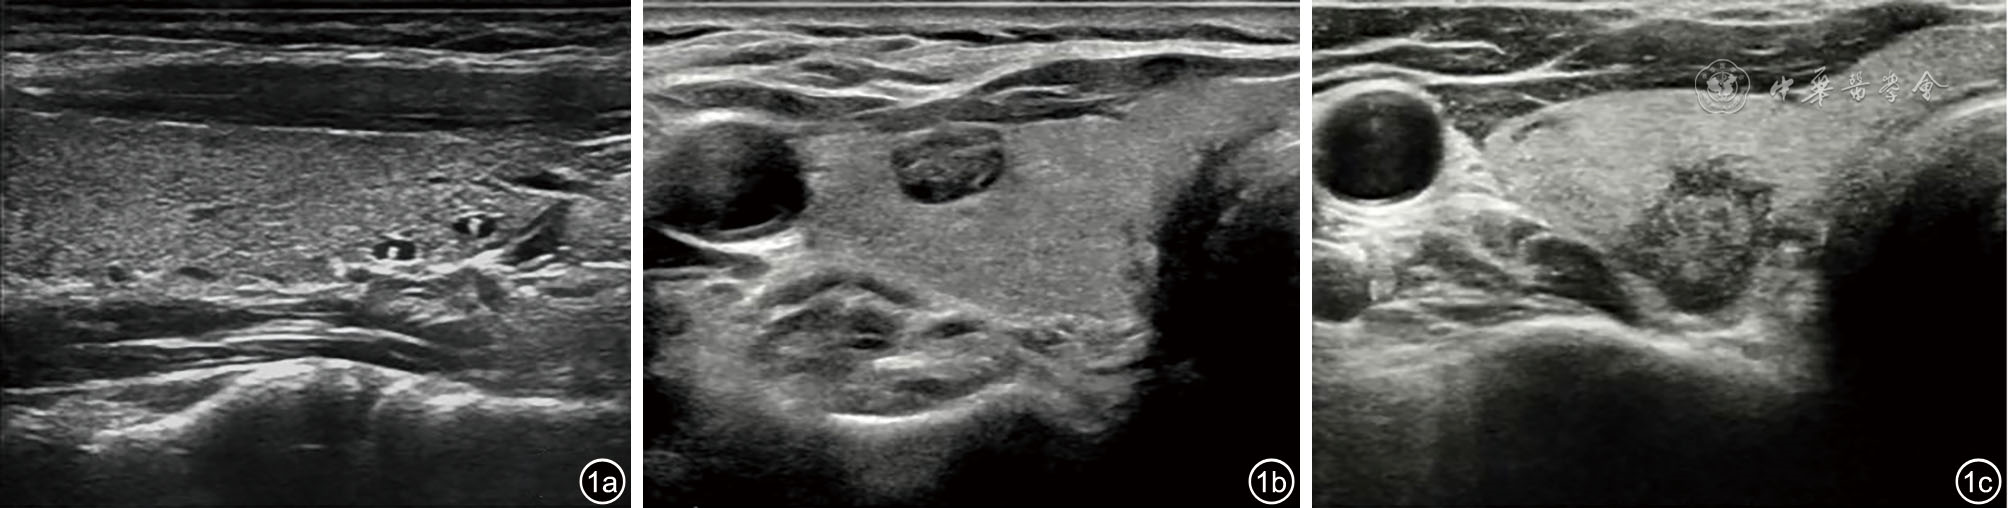

本研究选取2024年3月1日至2025年1月31日期间在北京大学第三医院超声医学科进修学习的117名进修医师作为调查对象。进修医师进修学习时间均为6个月,承担门诊超声报告记录员的工作,均可熟练使用本院制定的甲状腺结节结构化报告模板(图1)。

图1 基于甲状腺结节超声恶性危险分层的中国指南(C-TIRADS)词典的甲状腺结节超声结构化报告临床应用举例。图a结节描述为“甲状腺右叶可见多发结节,大者大小约0.3 cm×0.2 cm×0.1 cm(头足径×左右径×前后径),呈囊性,呈无回声,结节边缘光整,无声晕,纵横比≤1,结节内可见点状强回声伴彗星尾,结节内未见明显血流信号”,结节符合C-TIRADS 2类,考虑胶质囊肿;图b结节描述为“甲状腺右叶可见一结节,大小约0.8 cm×0.7 cm×0.4 cm(头足径×左右径×前后径),呈海绵状,结节边缘光整,无声晕,纵横比≤1,结节内无局灶强回声,结节内可见较丰富血流信号”,结节符合C-TIRADS 3类,考虑结节性甲状腺肿;图c结节描述为“甲状腺右叶可见一结节,位于中部,与后被膜相邻,大小约1.2 cm×0.9 cm×1.0 cm(头足径×左右径×前后径),呈实性,呈低回声,结节边缘不规则,无声晕,纵横比>1,结节内可见点样强回声,结节内可见少量血流信号”,结节符合C-TIRADS 4C类,手术病理证实为甲状腺乳头状癌。对于C-TIRADS分类在4类及以上的结节,需如本例所示,描述结节的具体位置